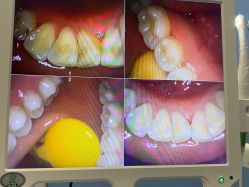

• 南京医科大学友谊整形外科医院

• -南京医科大学友谊整形外科医院